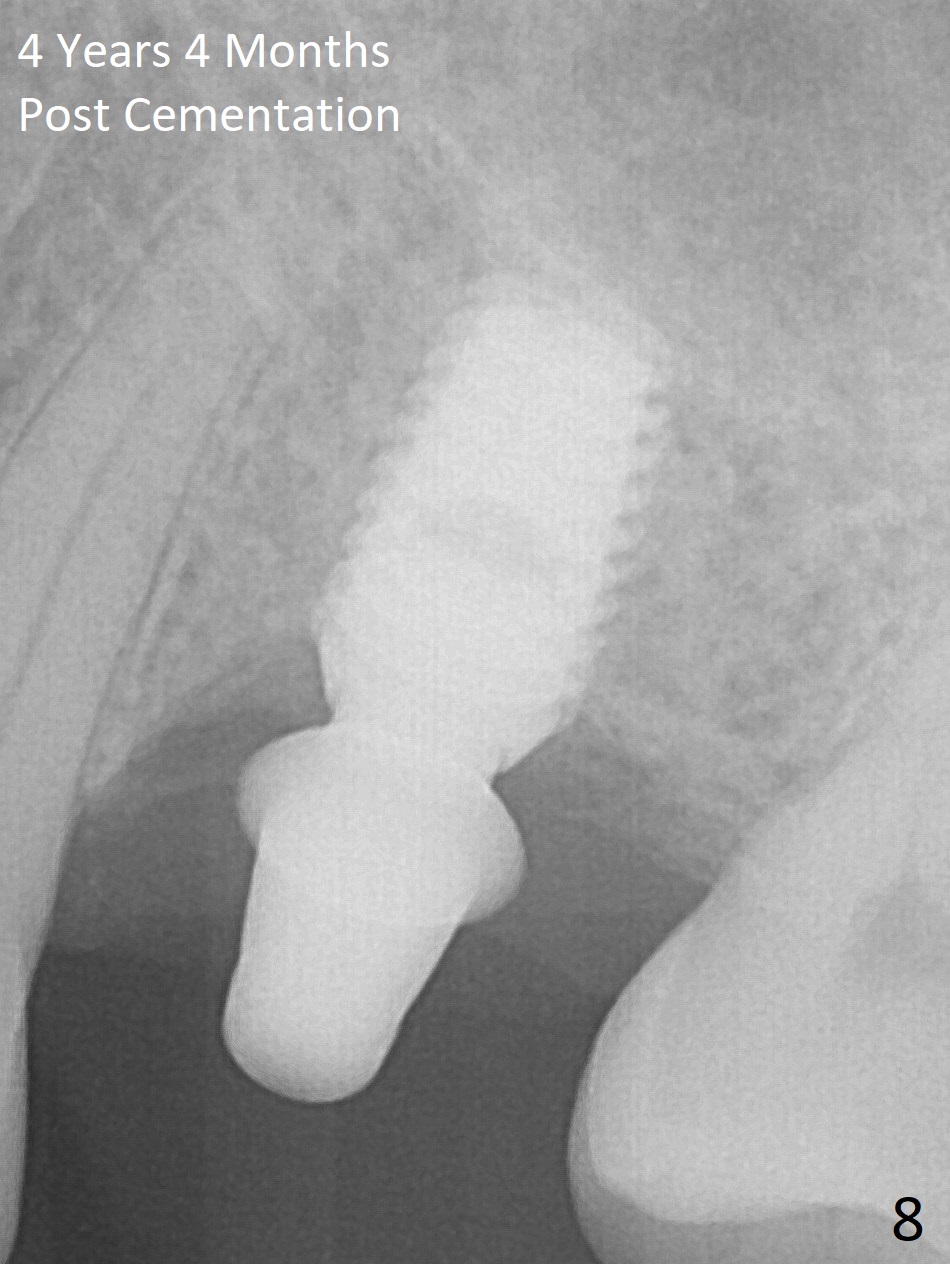

A 49-year-old man is an engineer. The tooth #14 is missing (Fig.1,2). He wonders how a one-rooted implant can replace a three-rooted tooth. Anyway, osteotomy is initiated at the site with 2.5 mm reamer in place (Fig.3). A 5x8 mm Bicon implant is placed (Fig.4). Seven and a half months later, the bone density next to the implant plateau appears to increase (Fig.5 arrowheads, as compared to Fig.4). The beauty of Bicon implant is that the crown (Fig.6 C) can be extraorally cemented to the abutment (A) prior to re-seating. Two years and 3 months post cementation, while no residual cement is visible, the bone density at the crest has increased (Fig.7 arrowheads). The crown is de-cemented 4 years 4 months post cementation; it appears that the abutment is small and short (5x2 mm 10 degree stealth). The bone density of the cortex around the implant (Fig.9 ^) is higher than that at #15 and #3.